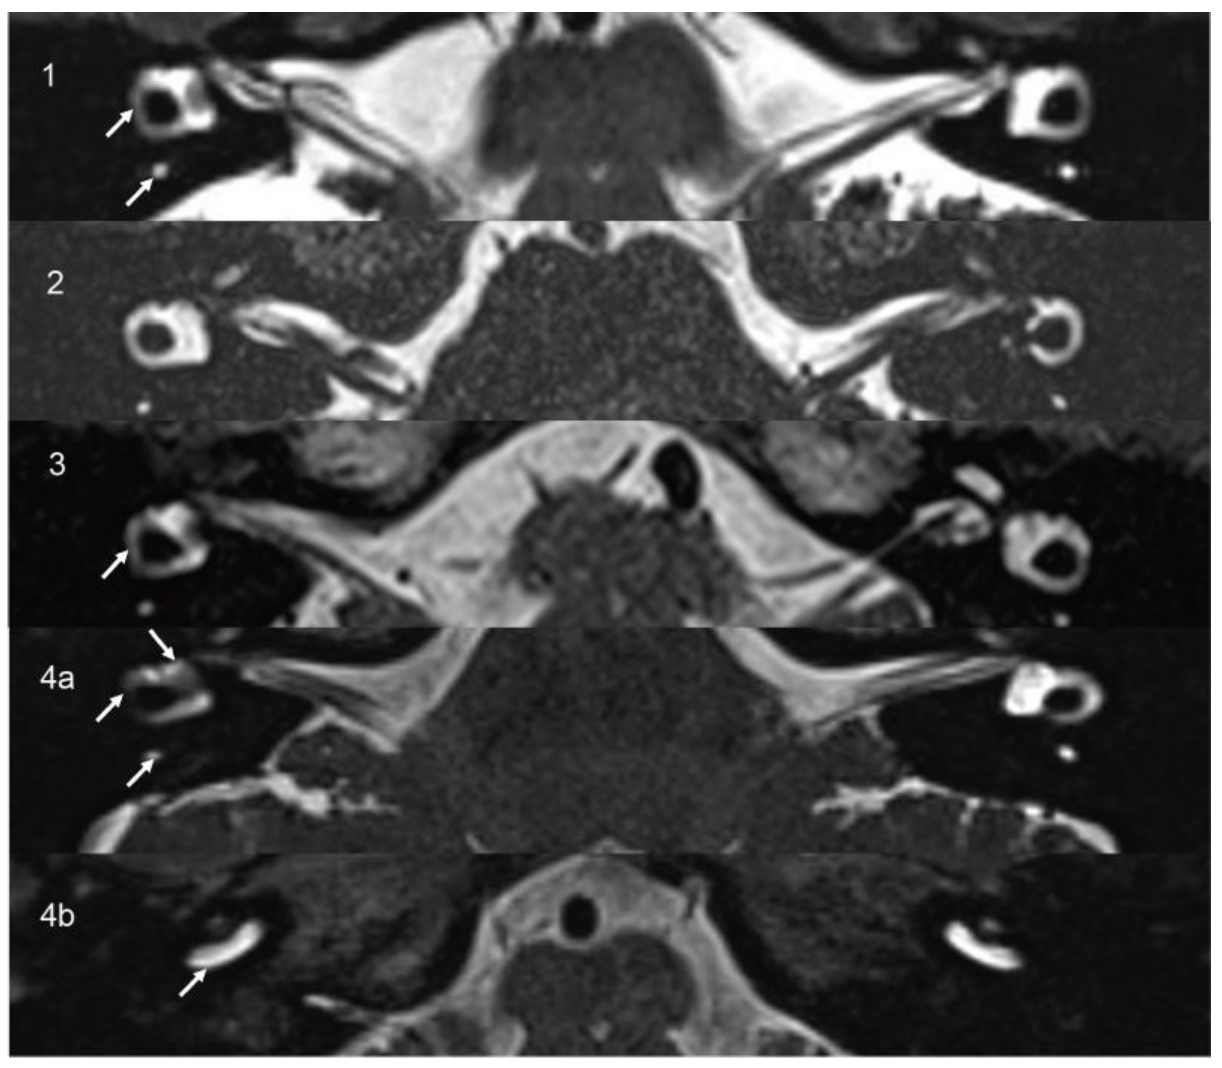

3.1.2. Case 2

| 2 | 14 | M | HL, aural fullness, recurrent vertigo | Left 4.3 mm | Intravestibular | 45 | LFHL | Decreased left mean VOR gain and CSs (0.7/0.64/0.75) | CP = 100% left side hypofunction | AR = 0.53 | Absent |